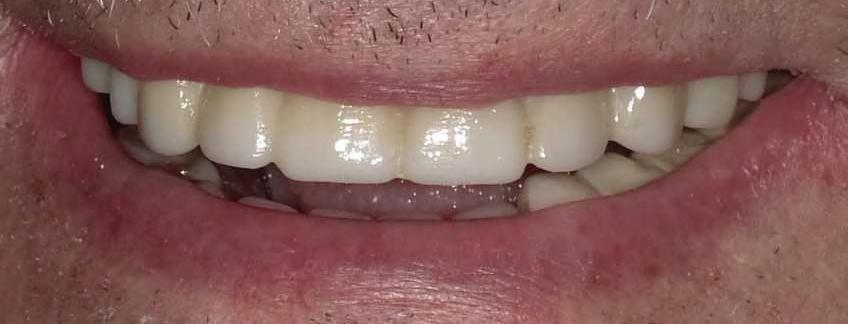

18 | Discover Your Perfect Full Arch Dental Solution | By Judy Yu, DMD, MBA

Affordability

In the past, individuals missing multiple teeth had limited options beyond uncomfortable and ill-fitting dentures. However, with the introduction of dental implants, removable dentures have become a viable choice. Although dentures may require adhesives and fall short of replicating the natural form and function of teeth, they offer affordability and easy removal for cleaning.

Four Implant Overdenture Secure and Functional

Stabilized overdentures resemble traditional removable dentures, but with a significant improvement in stability. By utilizing four locators on the underside of your denture plate, they securely attach to implant abutments. These snap-on dentures eliminate rocking, shifting, or rubbing, as the implants keep the appliance firmly in place. Overdentures enhance stability and functionality to approximately

Can just four implants replace all of the teeth on the top or the bottom of your mouth? Thanks to advances in dental implant technology, that answer is a resounding yes.

Tooth loss is extremely common among adults, especially as we age. Rather than living with the discomfort and hassles of dentures, many people are opting for what is called “all-onfour” dental implant restoration.

You do not need a dental implant for each and every one of your missing teeth. All you need is four precisely placed implants on the top of your mouth, and four on the bottom, to restore your full smile. That’s the beauty of the all-on-four. And because the implant is made of titanium, it has the unique ability to fuse to living bone and function as part of it. So eventually, the dental implant becomes part of the jawbone and serves as a strong, longlasting foundation for your new teeth.